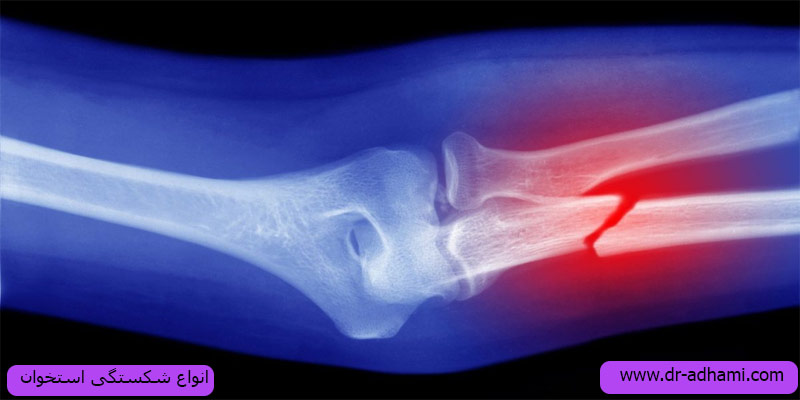

انواع شکستگی استخوان

شکستگی استخوانها را میتوان به چندین نوع تقسیم کرد، که شامل موارد زیر میشود:

شکستگی کامل: در این نوع شکستگی، استخوان به دو قسمت جداگانه تقسیم میشود. این نوع شکستگی ممکن است به صورت عرضی یا عمودی بروز کند. مقاله درمان شکستگی خرد شده را بخوانید.

شکستگی ناقص: در این نوع شکستگی، استخوان کاملاً شکسته نمیشود و به صورت ناقص ترک خورده یا خم میشود.شکستگی ناقص شامل شکستگیهایی مانند شکستگی خطی و شکستگی چرخهای است.

شکستگی باز: در این نوع شکستگی، استخوان شکسته است و قطعه شکسته از پوستی که استخوان را پوشانده، به بیرون میآید. این نوع شکستگی ممکن است با عفونت همراه باشد و نیاز به مراقبت و درمان جراحی فوری دارد.

شکستگی بسته: در این نوع شکستگی، استخوان شکسته است اما قطعه شکسته به بیرون نمیآید و پوست بر روی استخوان حفظ میشود. این نوع شکستگی ممکن است همراه با آسیبهای دیگر در بافتهای اطراف نظیر عضلات، عروق و اعصاب باشد.

شکستگی تراکمی: در این نوع شکستگی، استخوان فشرده میشود. این نوع شکستگی معمولاً در استخوانهایی که تحت فشار شدید قرار میگیرند رخ می دهد و معمولا در نتیجه سقوط یا حادثه اتفاق میافتد.

شکستگی ترکیبی: در این نوع شکستگی، استخوان شکسته است و قطعه شکسته از پوست بیرون میآید. علاوه بر این، این نوع شکستگی همراه با شکستگی در سایر اعضای بدن نظیر عضلات، عروق و اعصاب نیز میتواند باشد.